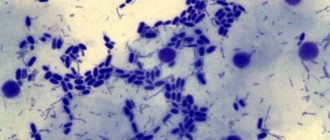

КАНДИДОЗ: Простой способ проверить наличие грибка в организме Очень важно вовремя проверять себя на